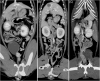

Methods: Multi-institutional, descriptive, retrospective case series study. Medical records were searched for a diagnosis of short colon on abdominal ultrasonography, computed tomography, endoscopy, autopsy, or a combination of these modalities.

Results: The median age of included cats was 12 years at the time of diagnosis. Diarrhea was the most common clinical sign (60/92; 65%), followed by vomiting (36/92; 39%), weight loss (36/92; 39%), and inappetence (24/92; 26%). Thirteen percent of cats (12/92) had no signs of gastrointestinal disease at the time of diagnosis. In addition to a shortened colonic length, 79% (66/84) of cats had concomitant colonic thickening on ultrasonographic examination. On colonoscopy, mucosal ulcerations of the colonic wall were seen in 39% (9/23) of cats. Histopathologically, all cats but 1 (diagnosed simultaneously with colonic small cell lymphoma) had lymphoplasmacytic colitis, and when small intestinal biopsies were performed, concurrent lymphoplasmacytic enteritis or small cell lymphoma of the small intestine.